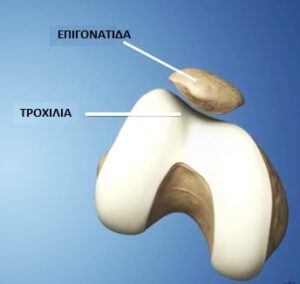

Είναι μέρος της άρθρωσης του γόνατος στην πρόσθια επιφάνειά του. Αποτελεί την άρθρωση μεταξύ επιγονατίδας και μηρού. Συγκεκριμένα, η οπίσθια επιφάνεια της επιγονατίδας, με μορφή «καρίνας», αρθρώνεται με την πρόσθια επιφάνεια του μηρού σε μια υποδοχή που ονομάζεται τροχιλία. (εικόνα 1 ). Η επιγονατίδα λειτουργεί σαν «υπομόχλιο» κατά την κάμψη – έκταση του γόνατος, ενισχύοντας τη δράση του εκτατικού μηχανισμού. Πρακτικά δηλαδή ενισχύει την έκταση (το «τέντωμα») του γόνατος υπό τη δράση του τετρακεφάλου μυός. (εικόνα 2 ). Η άρθρωση δέχεται πολύ ισχυρά συμπιεστικά φορτία. Είναι ενδεικτικό ότι ο χόνδρος που καλύπτει την οπίσθια επιφάνεια της επιγονατίδας είναι ο παχύτερος σε όλο το ανθρώπινο σώμα, ακριβώς για να μπορέσει να ανταποκριθεί σε αυτά τα φορτία.